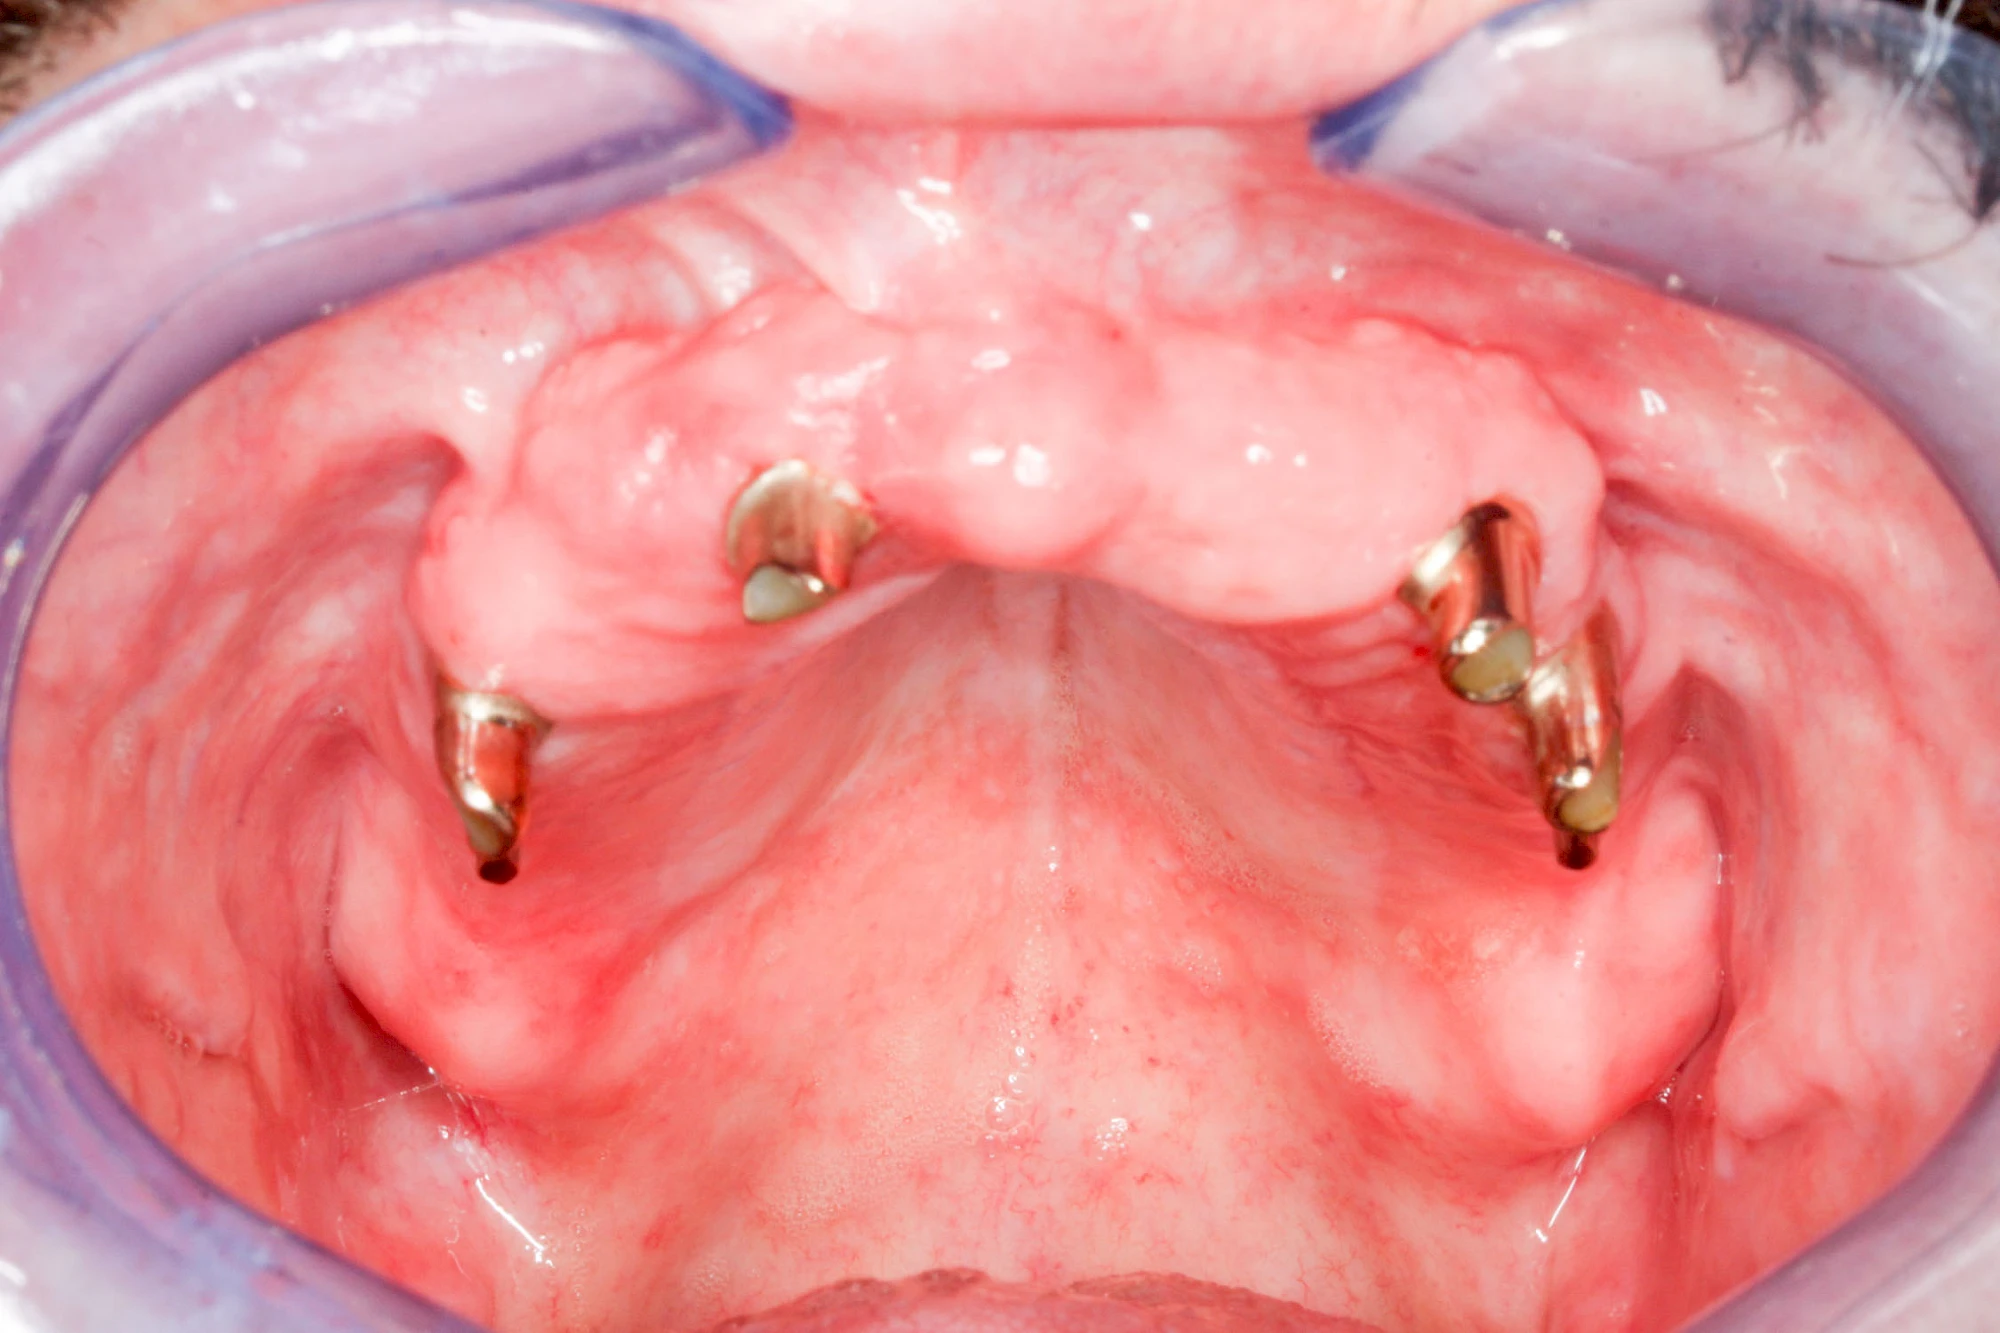

Implantate: Prothesen

Bei herausnehmbaren Prothesen werden Implantate eingesetzt, um den Halt und den Tragekomfort der Prothesen zu verbessern. Dazu kommen verschiedene Verbindungselemente zum Einsatz:

- Teleskope

- Kugelköpfe

- Tellerförmige Lokatoren

- Stege

- Magnete (selten)

Neben rein implantat-getragenen zahnärztlichen Versorgungen werden bei herausnehmbaren Prothesen Implantate auch in Sinne einer "strategischen Pfeilervermehrung" ergänzend zu eigenen Zähnen zur Verankerung eines Zahnersatzes genutzt.

Varianten zur Verankerung von abnehmbarem Zahnersatz auf Implantaten